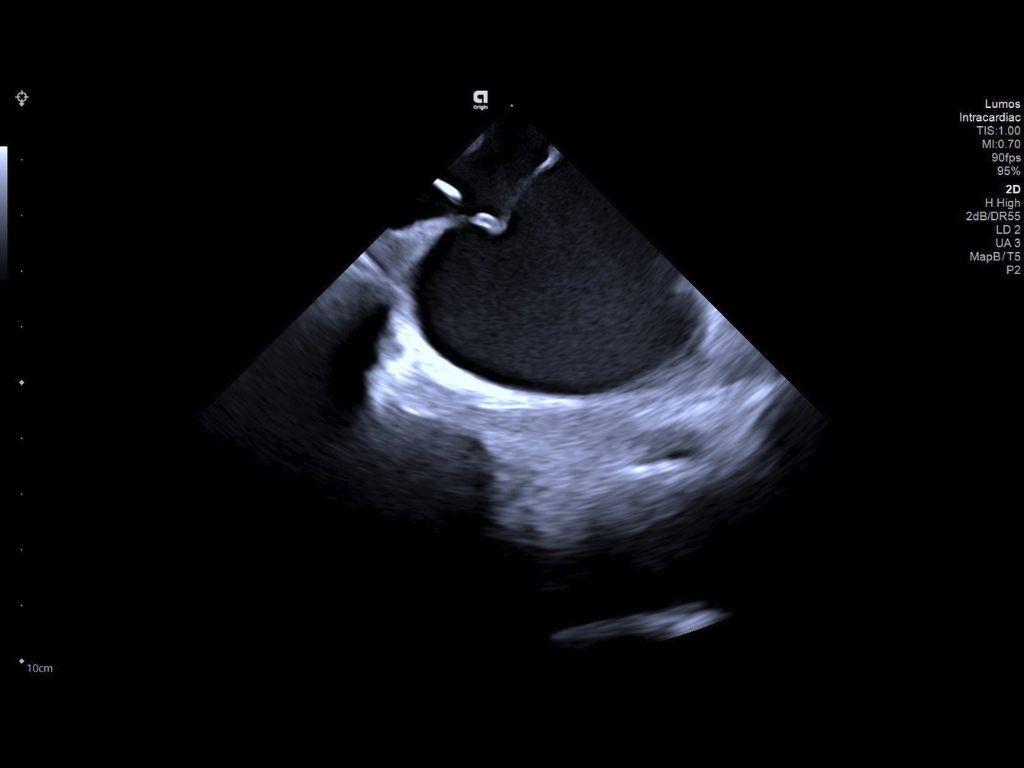

2D LV with ablation catheter

Left ventricle with ablation catheter visualization